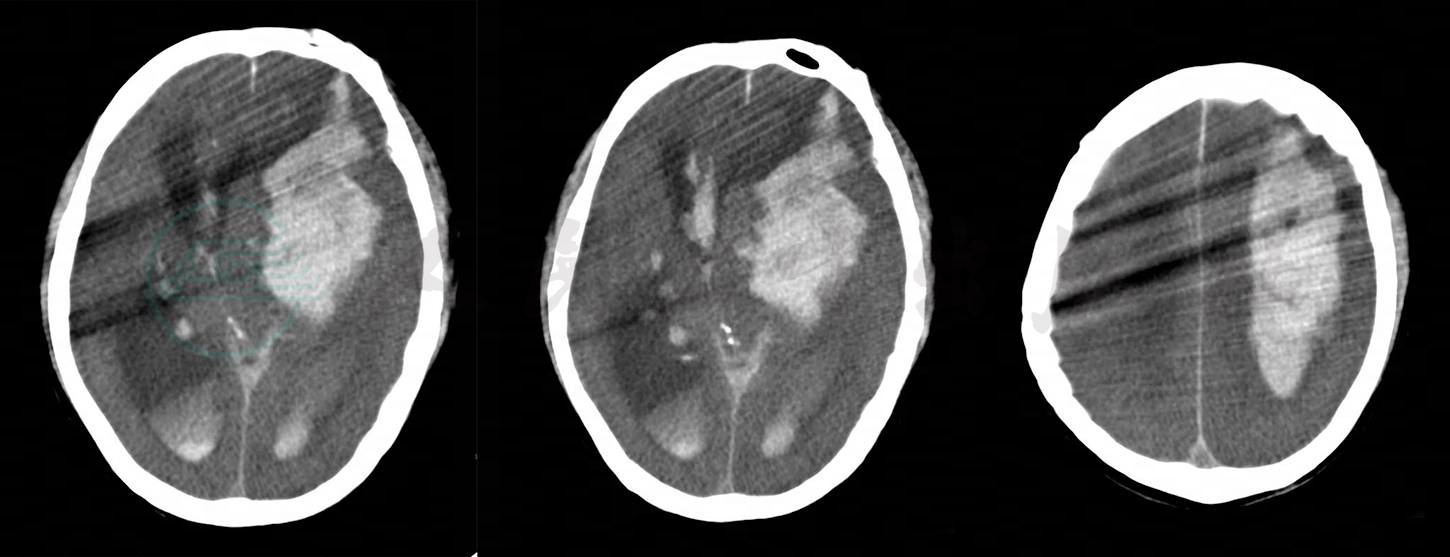

体格检查:体温37℃,脉搏98次/分,呼吸20次/分,血压150/96mmHg。神志模糊,问话少答,能认识儿子,但地点定向欠准确。心、肺、腹检查未见明显异常。四肢震颤,双手摸索样动作,神经系统检查不配合。考虑为酒精戒断反应,予临时肌内注射氟哌啶醇注射液2.5mg、静滴0.9%氯化钠注射液100ml加地西泮注射液10mg对症处理。据患者陪护反映,用药后患者安静入睡,且整晚鼾声不断。凌晨5点40分,护士查房多次呼叫患者无应答,并出现喷射样呕吐,小便解在床上。值班医生立即进行体格检查:呼吸16次/分,脉搏120次/分,血压170/110mmHg。患者呈中度昏迷,叹息样呼吸。双侧瞳孔不等大,左侧直径约5mm,对光反射消失,右侧直径3mm,对光反射迟钝。初步判断为脑血管病的可能性大,急查头颅CT后立即转入重症医学科抢救治疗。头颅CT结果为:考虑左大脑半球脑出血(出血中心位置在左侧基底节区)并破入脑室、蛛网膜下腔,继发大脑镰下疝、梗阻性脑积水(图1)。胸部CT:双肺多发感染性病变,建议治疗后复查;脂肪肝(重度)。

图1 脑出血